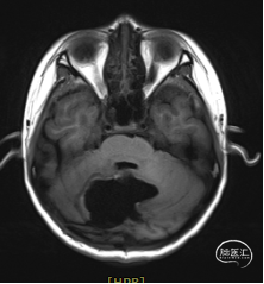

术后MRI